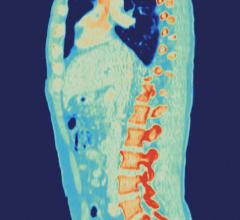

January 25, 2023 — On November 11th, 2022 at the Southern Hills Hospital in Las Vegas, USA, Robotic Spine Surgeon Dr ...